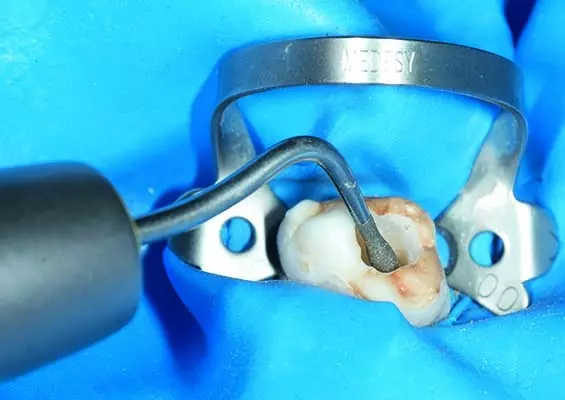

W tym wydaniu m.in: koferdam w adhezyjnych protokołach rekonstrukcyjnych, Low Dose – przełom w tomografii komputerowej CBCT, odpowiedzialność karna lekarza za błąd medyczny, wykorzystanie sonoabrazji w różnych dziedzinach stomatologii.